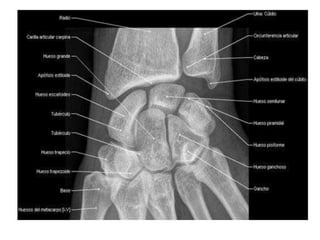

La articulación del la muñeca:

1.- Es de tipo sinovial condílea

2.- Se sitúa en el extremo distal del

radio y cubito, formando la

articulación radio-carpiana o también

radio – cubito – carpiana.

COMPONENTES

1.- Extremo distal del radio y el

disco articular de la articulación

radio-cubital.

2.- Hilera proximal de los huesos del

carpo (excepto el pisiforme).